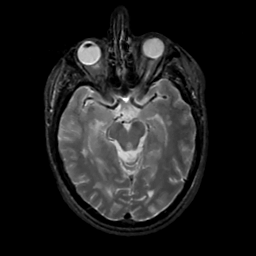

MR Study #2, February 17, 1991 -- Slice #20

Tour 1: Next/Previous/Start: This is a tour of the lesions of multiple sclerosis. Look at the "temporal" movie (time-cine) to see any changes occurring during one year's time. Look at the "spatial" movie (choose "cine", next to the sagittal image) to see the whole brain. There are a few small regions of high signal in temporal white matter, but, at this level, the image is mostly normal. On our next stop, we will see a larger lesion.